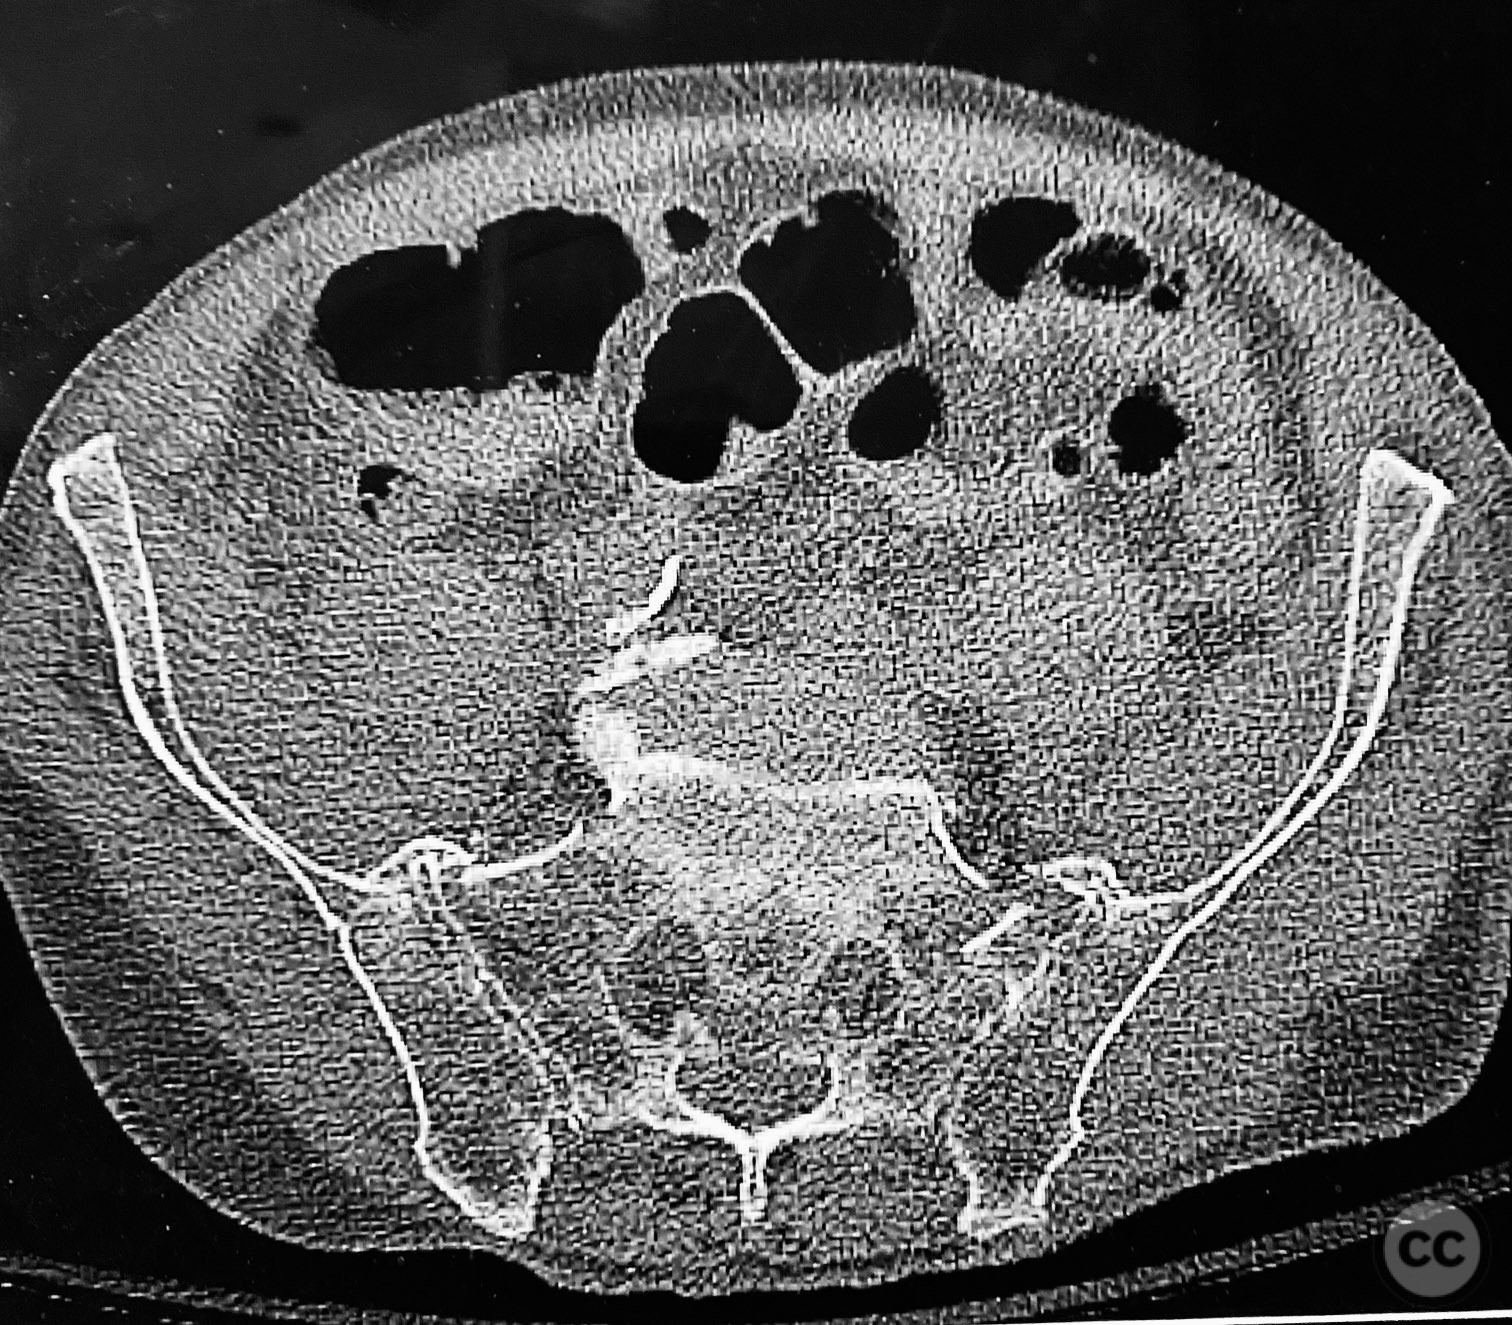

Clinical and radiological findings:  An elderly patient presented with a complex upper sacral fracture characterized by oblique fracture pathways bilaterally, described as a "UYH+pattern" fracture. The patient exhibited compromised bone quality consistent with age-related osteopenia or osteoporosis. Initial clinical assessment prioritized pain control and early mobilization. Radiological evaluation, including computed tomography (CT), confirmed the oblique orientation of the upper sacral fracture lines and their bilateral extension. No neurovascular compromise was reported.

Planning remarks:  The preoperative plan involved percutaneous stabilization of the bilateral oblique upper sacral fractures using a cannulated, articulated intramedullary fixation device (CurvaFix). The anatomical approach was planned to accommodate the oblique trajectory of the sacral fracture pathways, with bilateral guide pin placement under fluoroscopic guidance, followed by device insertion and locking.

Anatomical surgical approach:  Percutaneous access was established over the dorsal aspect of the pelvis. Small incisions were made lateral to the sacrum, and soft tissue dissection was performed to the level of the os sacrum. Guide pins were advanced under fluoroscopic control along the oblique upper sacral corridors bilaterally. The cannulated CurvaFix device was inserted over each guide pin, articulated to match the oblique fracture pathway, and subsequently locked in situ according to the manufacturer’s specifications.